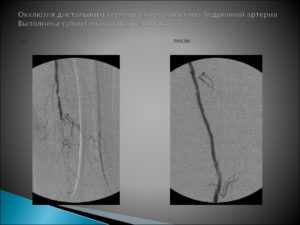

Окклюзия артерий нижних конечностей: причины, симптомы, лечение и профилактика